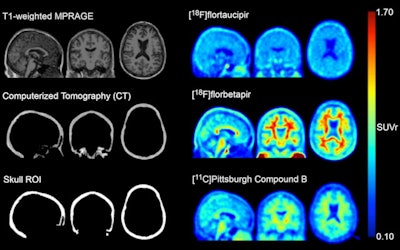

The group first created "skull masks" from CT scans to define regions of interest (ROIs) in 313 cognitively normal and mildly impaired men (n = 196) and women (n = 177). All subjects underwent amyloid PET (F-18 florbetapir and Pittsburgh compound B) and tau PET imaging as part of their participation in trials.

The masks were then used to quantify skull uptake among subjects of flortaucipir F-18 (Tauvid, Avid Radiopharmaceuticals), which is the most widely used tau PET tracer.